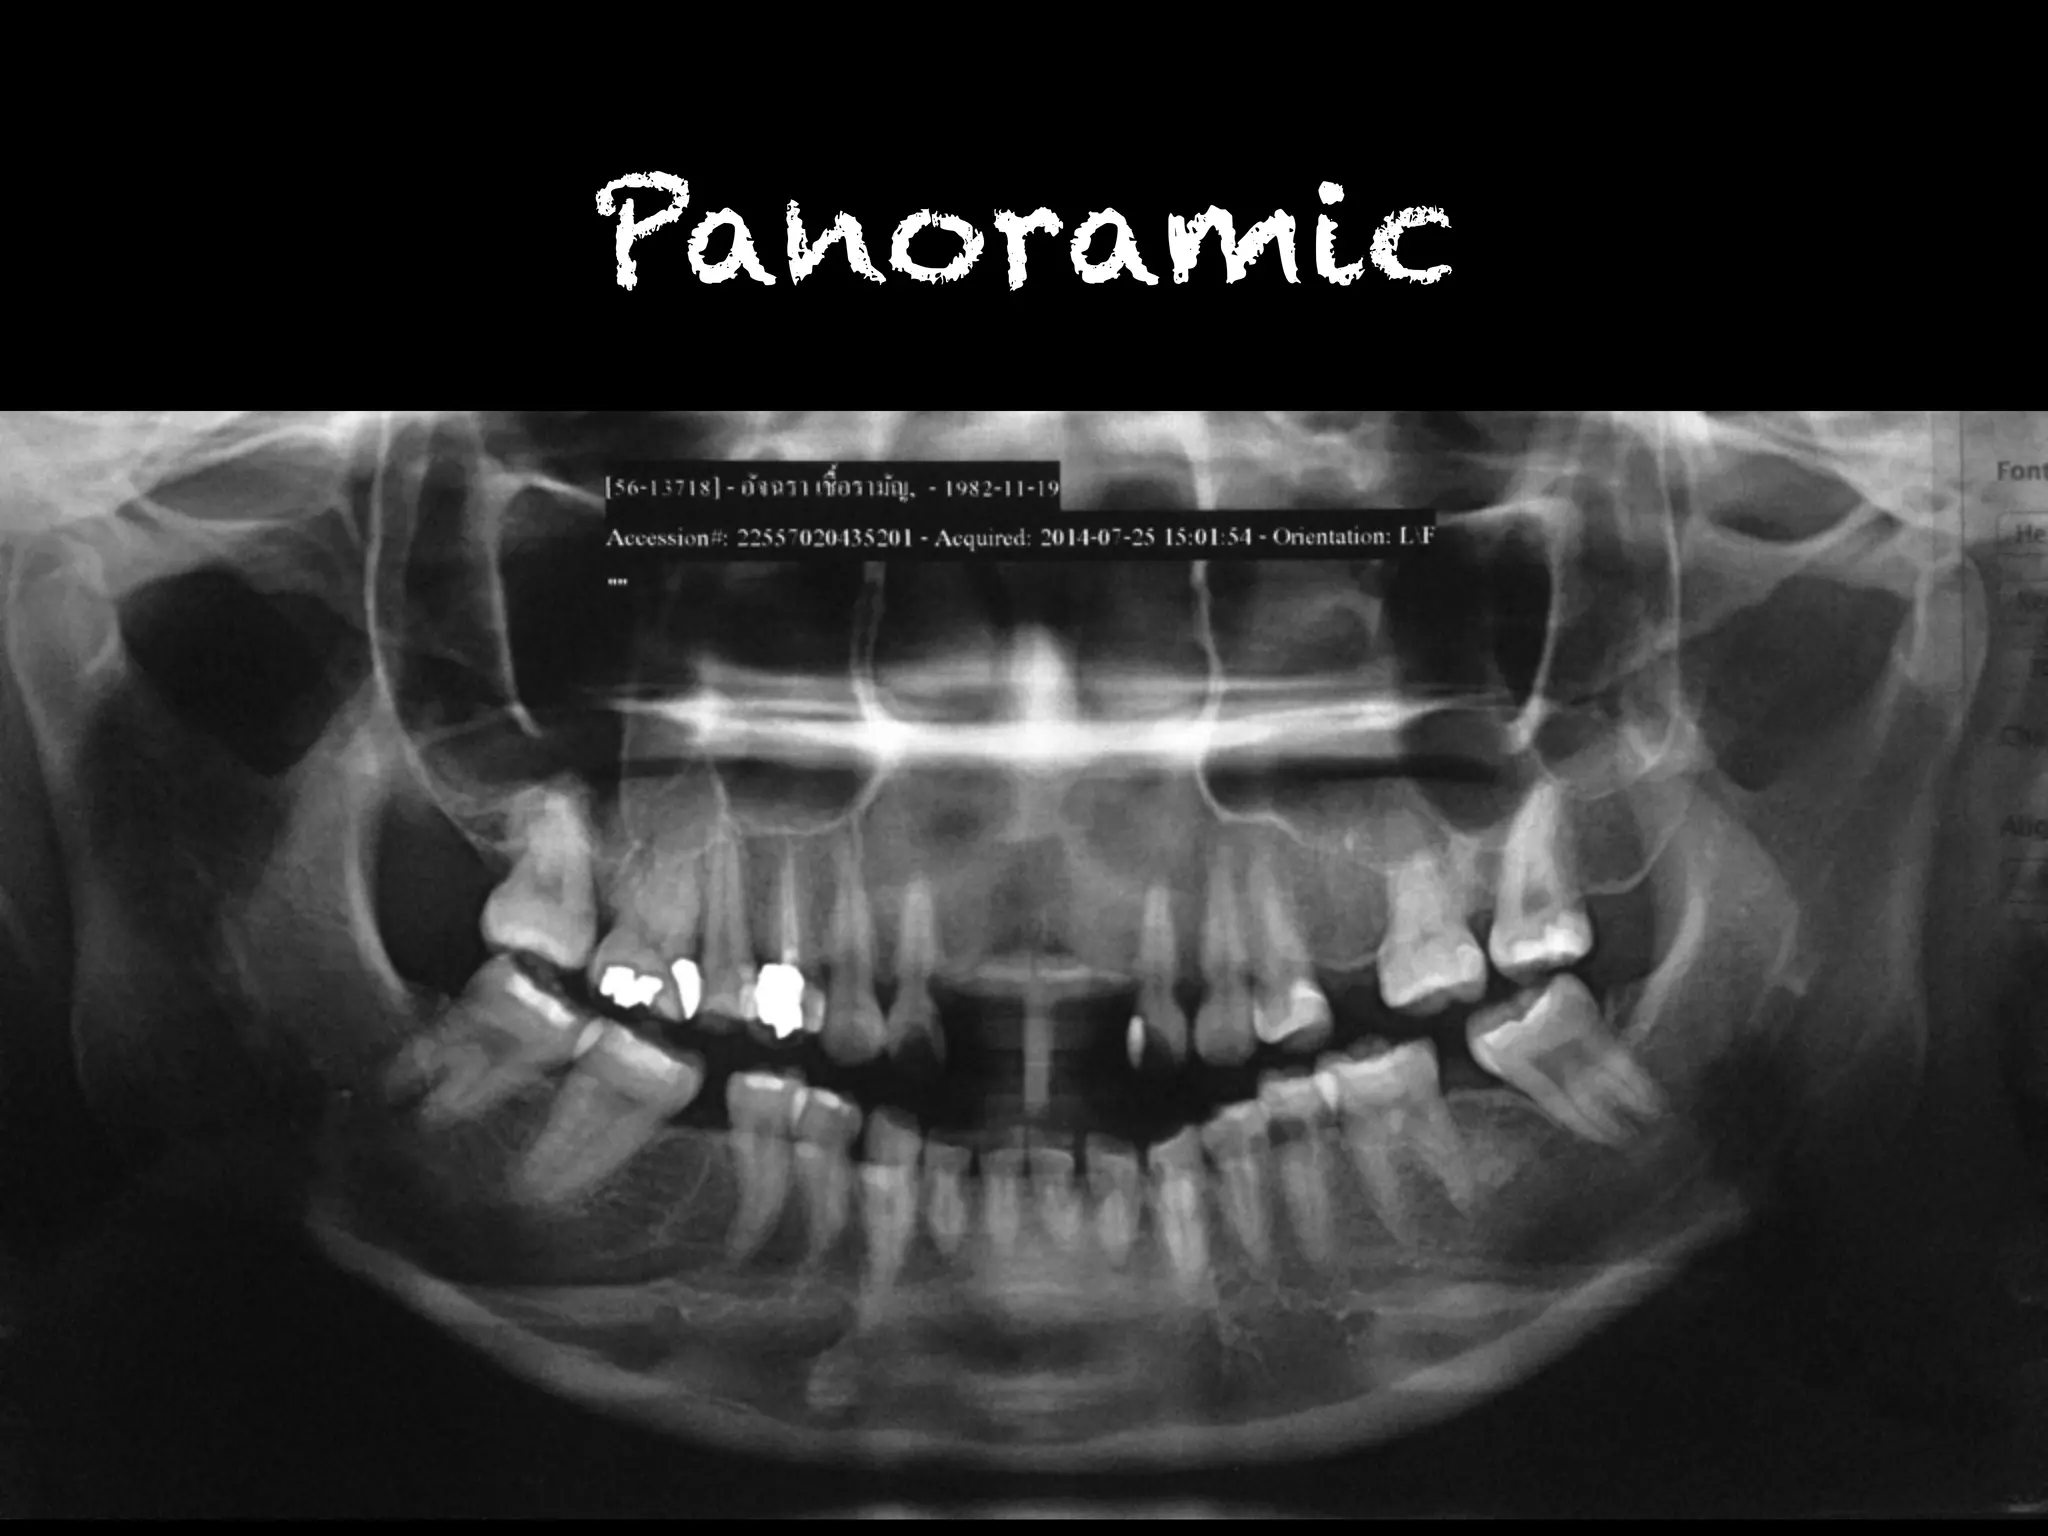

พบรอยโรคโปร่งรังสีที่บริเวณคอฟัน ฟันซี่

12MD,13M,22MD,23M,31MD,32MD,33MD,

41MD,42MD,43MD,34MD,35MD,36MD,

48M

Panoramic